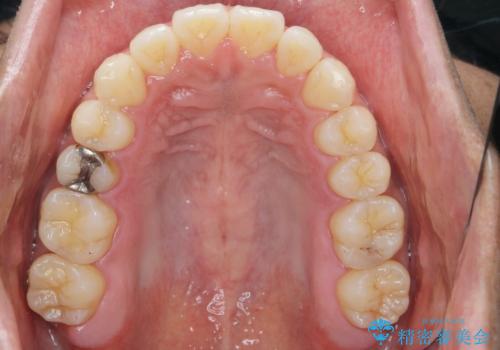

- 前歯のガタつきをきれいにしたい、と矯正治療を希望され来院されました。

マウスピース矯正インビザラインを用いてガタつきをきれいに並べていきます。

外側に傾斜していた前歯の角度も良くなり、「前歯の見た目が良くなった。」、と喜んでいただくことができました。